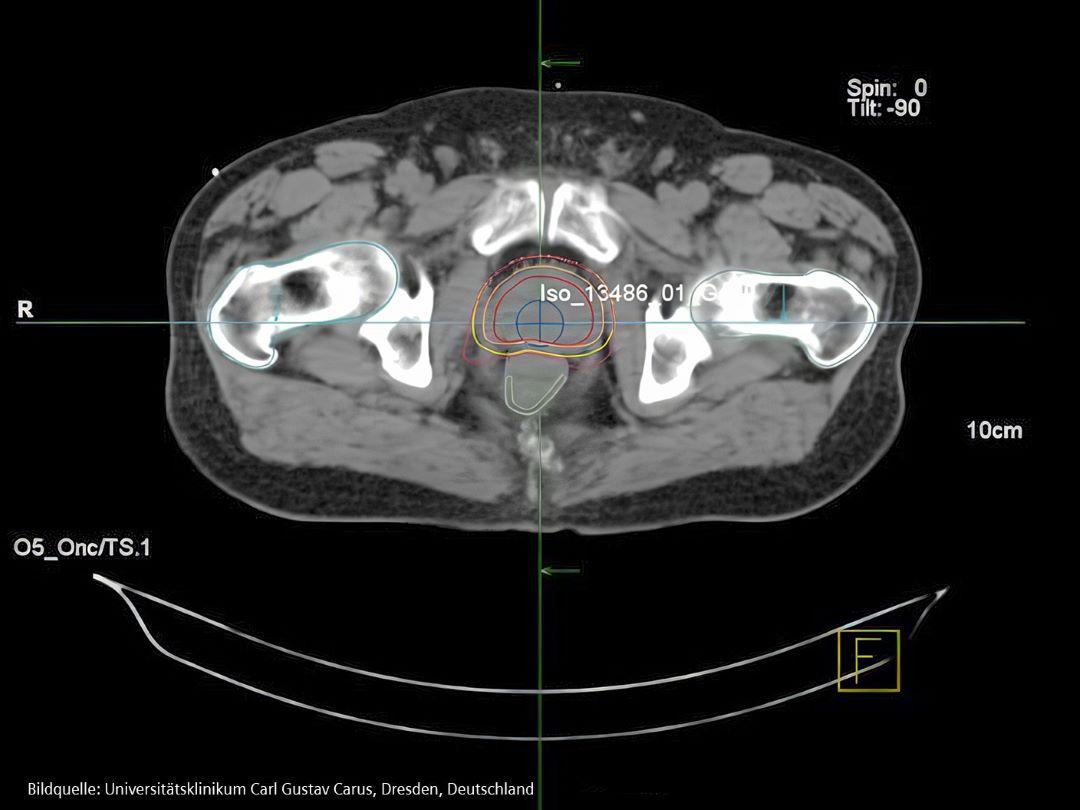

Behandlung

Frühzeitig erkannter Prostatakrebs ist sehr gut heilbar.

VARIAN EclipseTM IMRT (Intensity Modulated Radiotherapy) Plan für Prostatakrebspatienten.1